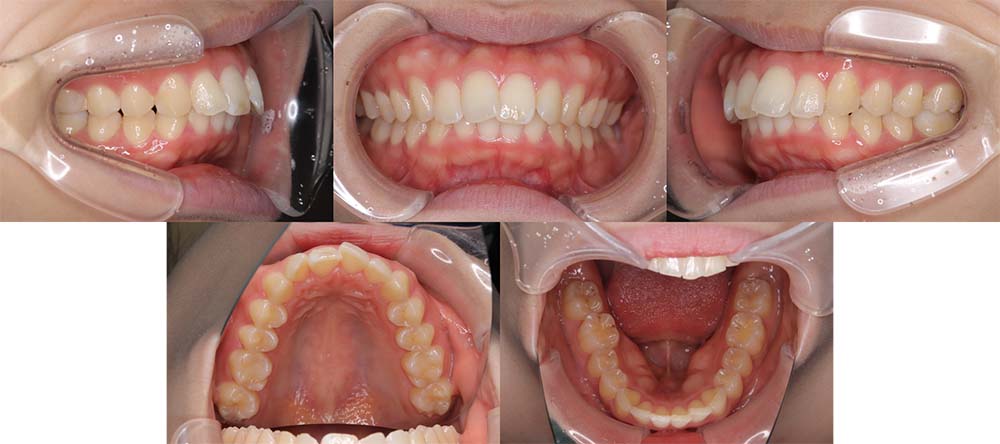

| 症例分類 | 叢生、口唇突出 |

| 診断名 | 上下前歯部叢生 |

| 主訴 | 下の前歯がガタガタ、横から見ると口が前に出ている |

| 年齢 | 23歳0ヶ月 |

| 性別 | 女性 |

| 抜歯部位 | 上下左右の第一小臼歯(4本) |

| 使用装置 | 上が裏側、下が表側のワイヤー装置 |

| 治療期間 | 2年7ヶ月 |

| 保定装置 | 固定式保定装置、取り外し式保定装置(8時間) |

| 費用 |

[検査・診断料] ¥49,500 [基本施術料] ¥1,056,000 [調整料] ¥4,400/回 [抜歯] ¥5,500/本 [保定装置] ¥55,000(税込) 抜歯や虫歯治療は他院にて費用が別途かかります。(抜歯¥4,000〜10,000/本)

上下軽度叢生と口唇突出感があるため、上顎両側第一小臼歯と下顎両側第一小臼歯を抜去して治療を行いました。

口唇突出感が改善され、口唇閉鎖不全も無くなりました。

スペースクローズに時間がかかってしまい、予定より治療期間がかかってしまいしたが、問題なく咬合させることができました。